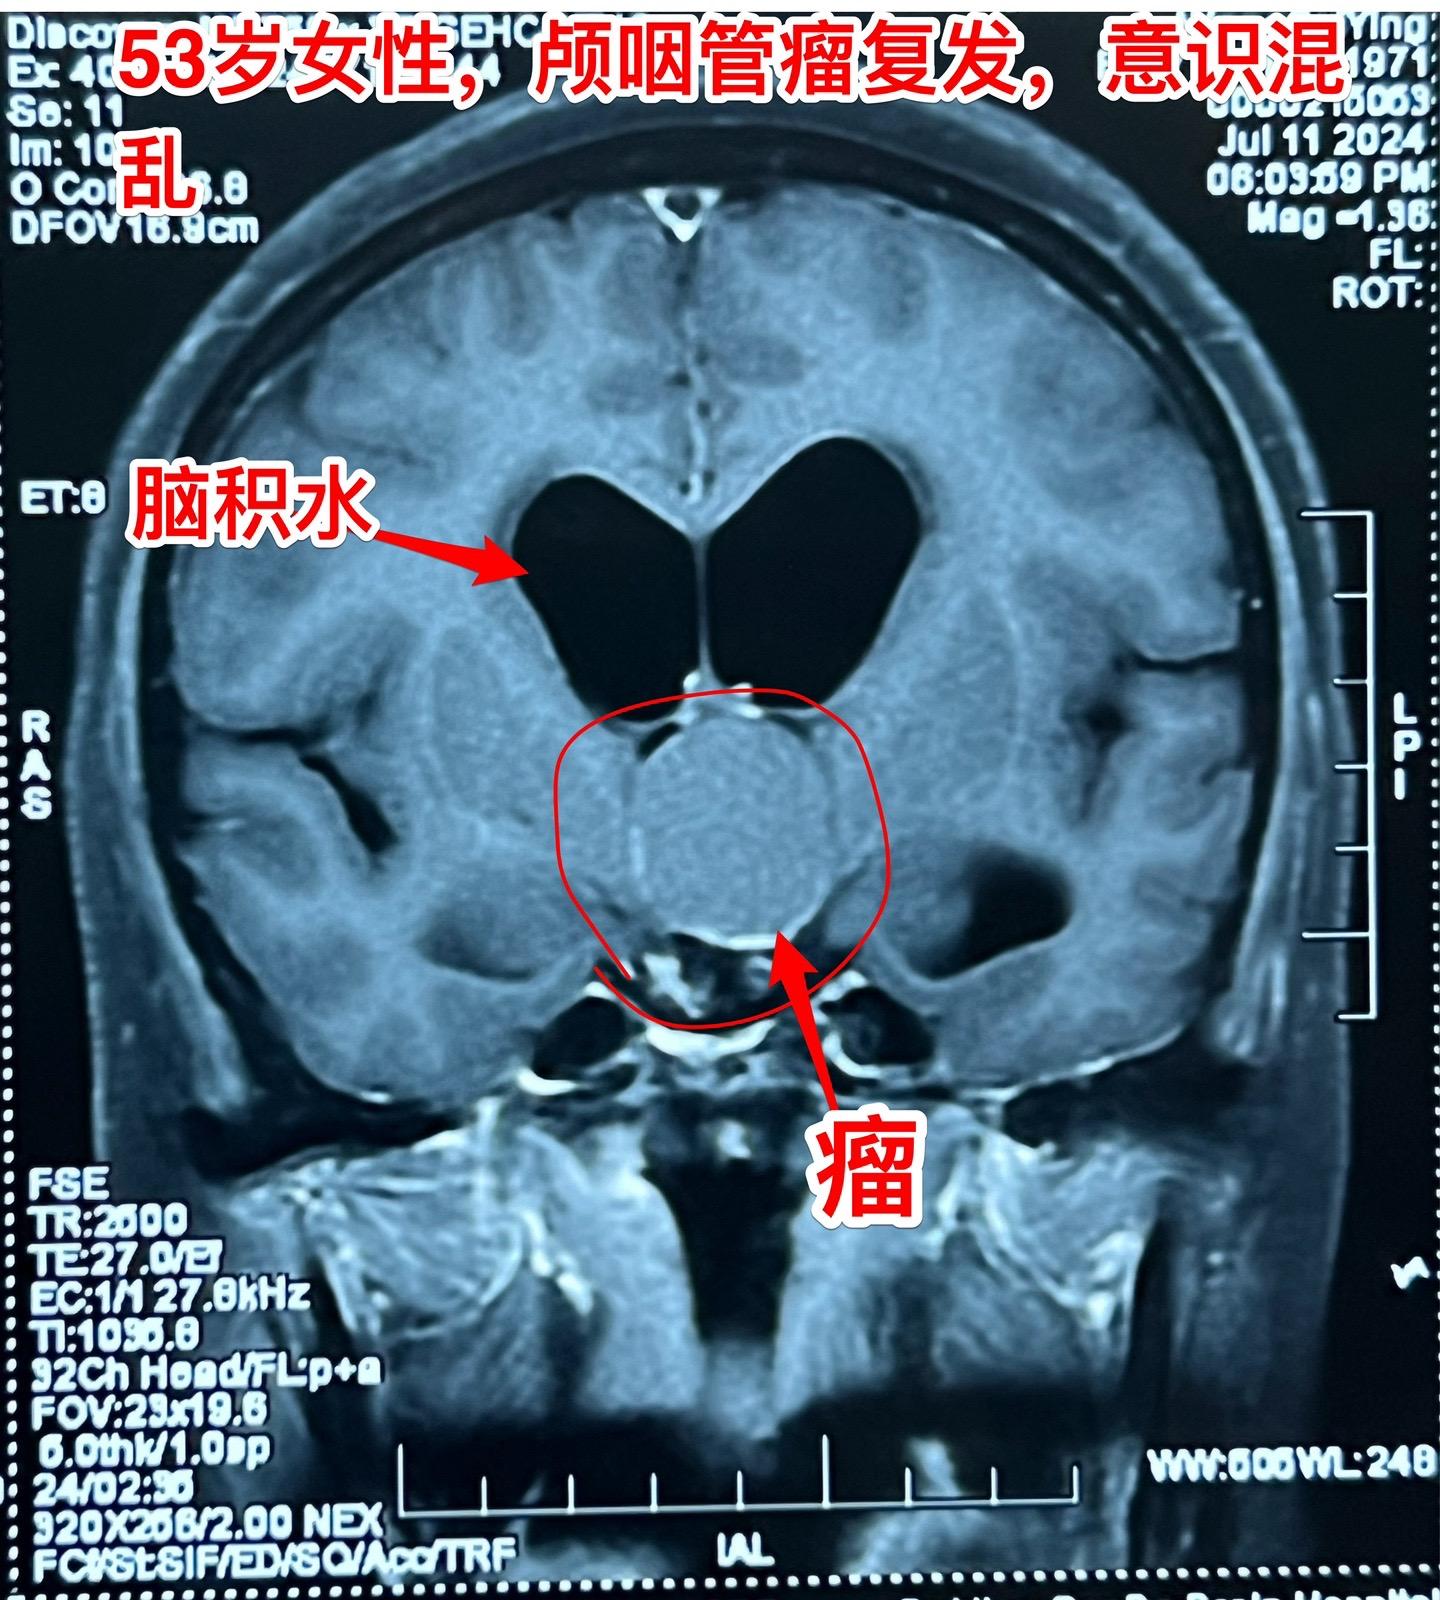

颅咽管瘤复发了怎么就意识混乱了?安徽省宿州的女性,53岁,14年前曾经作过颅咽管瘤切除手术。近10天她突然出现意识混乱,胡说,尿失禁,行走不稳。这是为什么呢? 其实她的病并不突然。 14年前作过颅咽管瘤切除手术,肿瘤有残留,就作了伽马刀治疗。2015年肿瘤复发了,又作了一次伽马刀治疗。之后生活质量还不错,能够作家务。 住院前10天她突然出现意识混乱,胡言乱语,同时还有尿失禁,行走困难。到医院去作头C T检查,发现肿瘤复发了,而且还造成了脑积水。